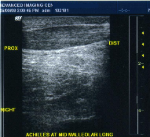

Achilles Tendon: Tendonitis, marked swelling of the tendon belly proximal to the insertion

Achilles Tendon: long axis correlation to transverse view must be obtained.